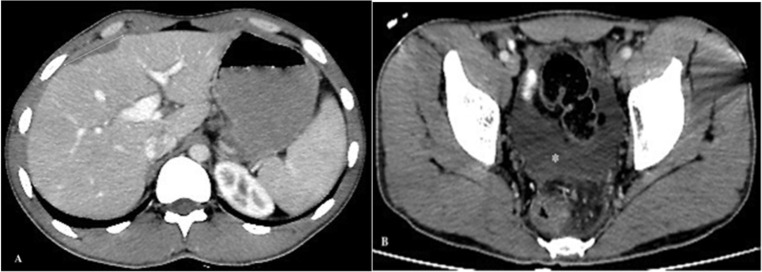

出血是一种非常罕见的法氏囊属(F. hepatica 或 F. gigantica)感染并发症。我们在此报告了土耳其东南部迪亚巴克尔省的三例由肝期法氏囊属感染引起的肝囊下出血病例,其中两例为女性,年龄分别为22岁、66岁和84岁。他们的症状包括右上腹疼痛(3 例)、恶心(1 例)和呕吐(2 例),持续时间从 6 小时到 15 天不等。所有患者的临床表现从中度腹痛到低血容量性休克和缺血性肝炎,均在支持性治疗后得到改善,无需手术。他们在服用曲克芦苯咪唑后,临床和化验指标均完全恢复。总之,肝病出血的病因应考虑法氏囊属感染。

Bleeding is a very rare complication of Fasciola species (F. hepatica or F. gigantica) infection. We present here three cases of subcapsular liver bleeding caused by the hepatic phase of Fasciola spp. infection in patients, two of whom were women, aged 22, 66, and 84 years in Diyarbakir Province, southeastern Turkey. They had symptoms of right upper quadrant pain (n = 3), nausea (n = 1), and vomiting (n = 2) for periods ranging from 6 hours to 15 days. All patients with clinical presentations ranging from moderate abdominal pain to hypovolemic shock and ischemic hepatitis were improved with supportive treatment without the need for surgery. They showed complete clinical and laboratory recovery after triclabendazole administration in their follow-up. In conclusion, Fasciola spp. infection should be considered in the etiology of bleeding from liver disease.